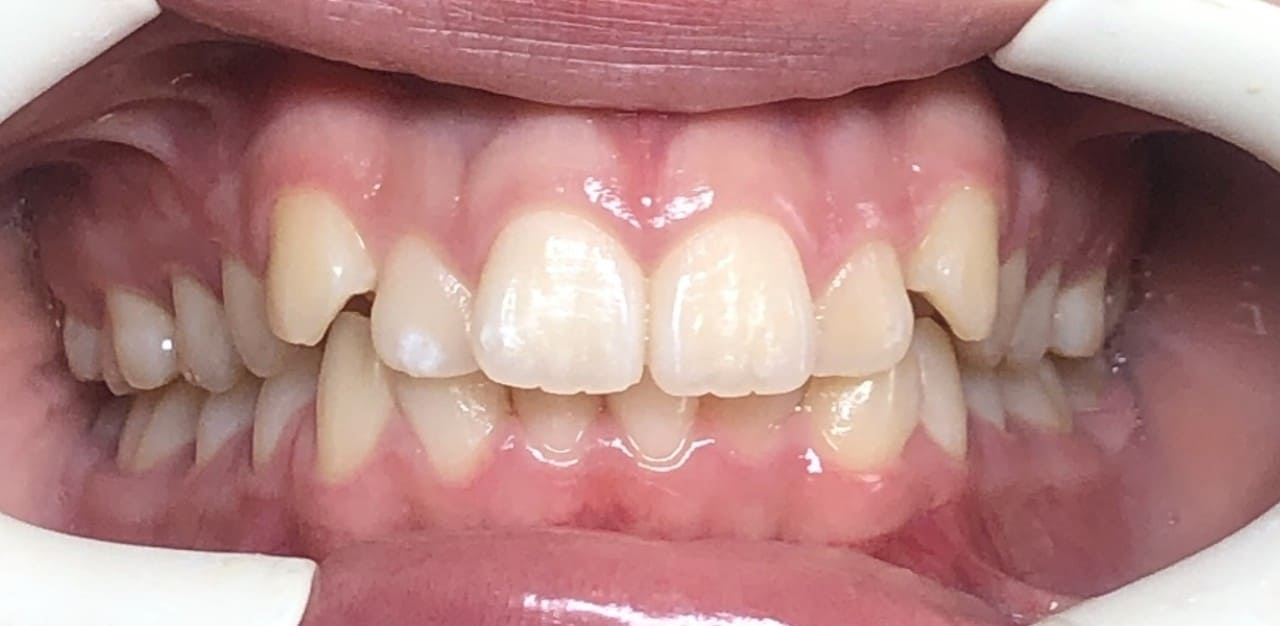

Initial

Final

Results achieved

- Class I relationship achieved

- Functional canine guidance on both sides

- Normal overjet and overbite achieved

- Deepbite improved

- Overjet improved

- Midlines coincident

- Curve of Spee leveled

- Arches aligned and coordinated

- Aesthetic smile line was achieved

- All treatment goals were achieved case